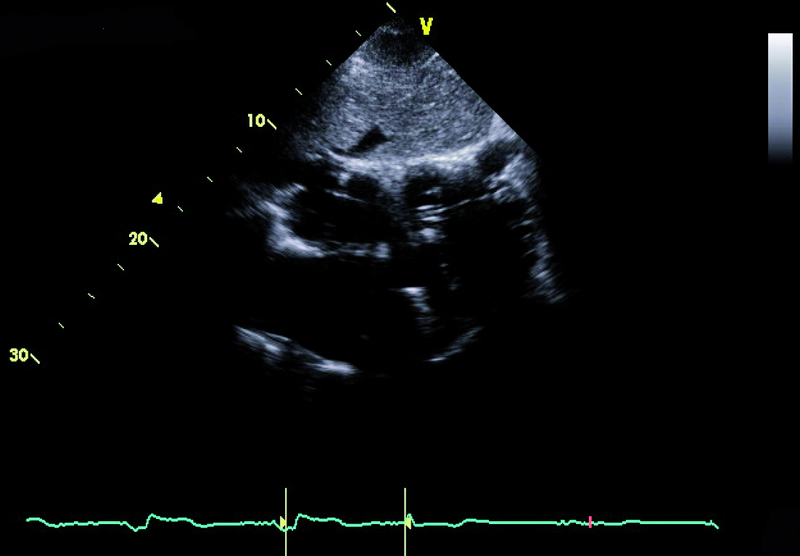

Mężczyzna, lat 59. Jakie patologie można rozpoznać na rycinach?

2. Niedomykalność zastawki mitralnej – przeciek okołozastawkowy (ryc. 2).

3. Niedomykalność zastawki trójdzielnej (ryc. 2).